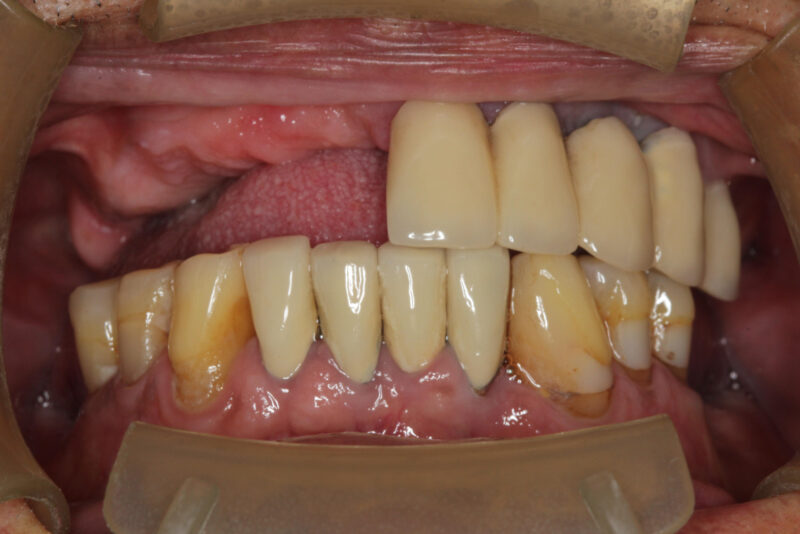

• Placed an implant and healing abutment and patient came with overgrown tissue on lingual which is not soft or hard but a bump. At first I thought it was an ill-fitting interim denture and adjusted. Also placed a soft liner. She came back 2 weeks later still there. So I placed a taller healing abutment and adjusted her existing denture to not…

Read more

• From the picture, it looks like some decent quality tissue that has built up over time. When you finish your new prosthesis and have proper tissue pressure everywhere, it might settle down slightly, but at this point, I would just leave it as it’s better to have that type of tissue than oral mucosa up against your locators. It looks like…

• Have you tried adjusting the tissue at all? You could just use a 15 blade and trim it down a bit. It’s not the end of the world to have the tissue bulging like that but it can be a nuisance